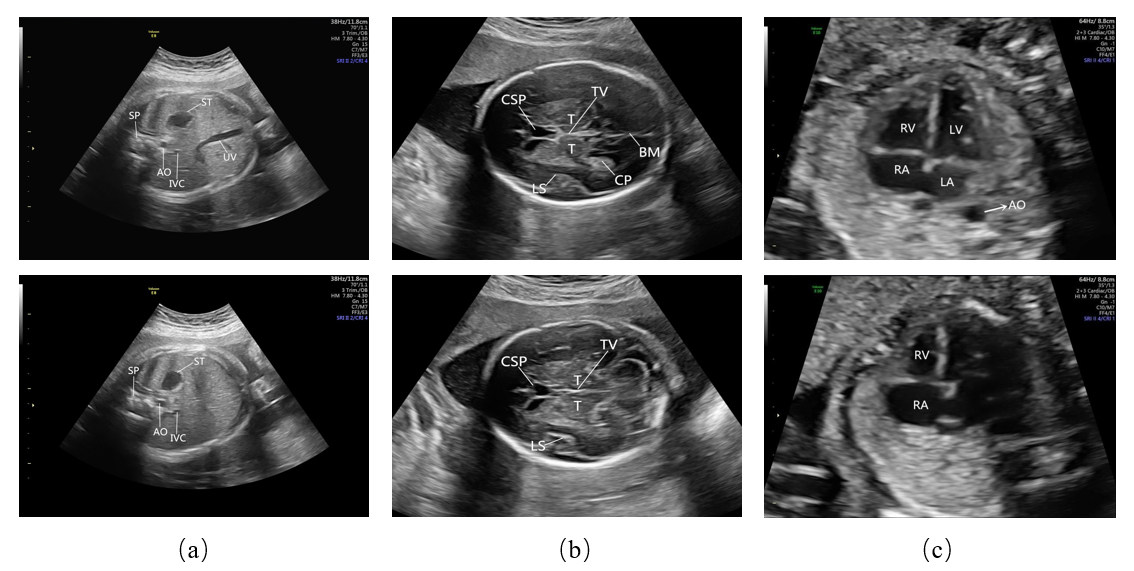

To obtain standard planes and assess the quality of FS images, it is necessary that all the essential anatomical structures in the imaging should appear full and remarkable with clear boundary [1]. For each medical section, there are different essential structures. In our research, we consider three medical sections: the heart section, the head section, and the abdominal section. The essential structures corresponding to these sections are given in Table 1. The list of essential anatomical structures used to evaluate the image quality is defined by the guideline [1] and further refined by two senior radiologists with more than ten years of experience of FS examination at the West China Second Hospital Sichuan University, Chengdu, China. A comparison of standard and non-standard planes can be illustrated in Fig. 1.